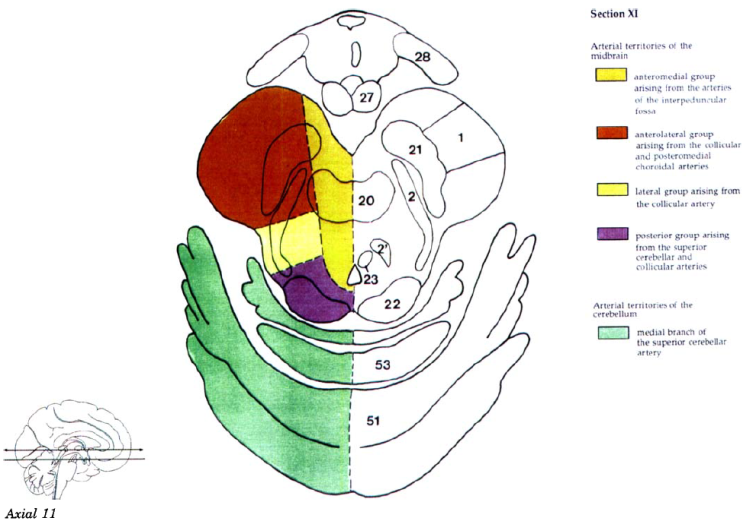

Cerebral vascular territories

Brainstem